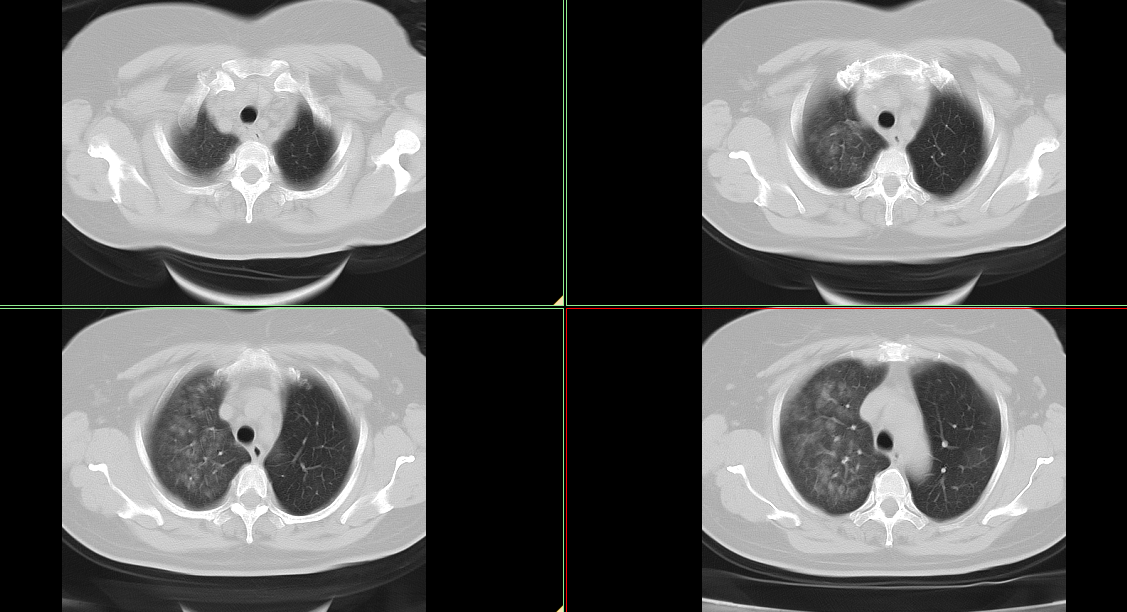

CT50232:肺部弥漫性病变待诊。

女性患者,55岁,咯血前来就诊。无发热、咳嗽等相关病史。既往病史不详。

不除外肺部转移可能,请追问病史(特别是妇科病史)

不除外肺部转移,请追问病史

肺水肿吧,左侧冠状动脉前降支有硬化

多考虑急性肺泡性肺水肿。

肺水肿,肺泡出血,肺泡蛋白沉着疹

左心室增大,肺水肿。

急性肺泡性肺水肿。